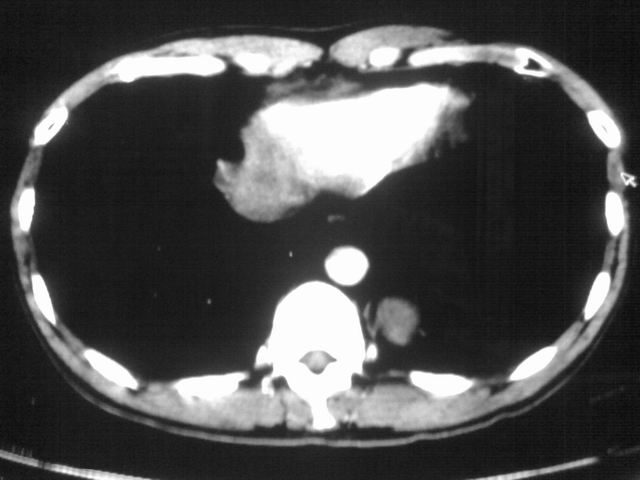

以下是引用苯小孩在2007-4-24 19:46:00的发言:[br]左下肺内侧基底段,见类圆形病灶,边缘清晰光滑.强化后轻中度强化.<平扫第4层面似有从腹主动脉相连血管影,可惜强化扫描这层没有抓住>考虑:左下肺隔离症.建议dsa或薄层强化重建观察.

以下是引用同在2007-4-24 20:11:00的发言:[br]考虑肺隔离症